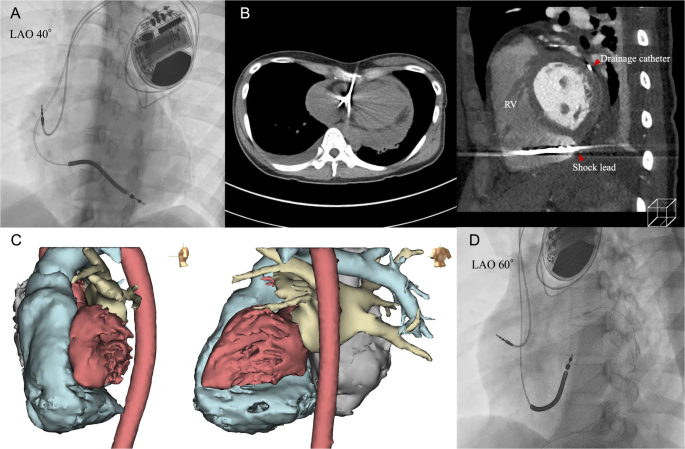

(A)植入时的左前斜位(LAO)40°透视图像,显示放电电极位于右心室间隔处。(B)左侧:非增强CT显示有心包积液;右侧:引流后的增强CT证实电极穿破了右心室下间隔壁并进入心包腔,由于右心室明显扩张,左侧心室心肌未受影响。(C)消融前的3D血流池CT图像用于手术规划,展示了用于矫正的偏移间隔平面。(D)在术中TTE引导下重新定位后的电极最终位置,采用个性化的左前斜位(LAO)60°投影显示。

一名30岁的女性患者出现运动诱发的持续性室性心动过速。经胸超声心动图(TTE)显示右心室(RV)明显扩大,进一步检查确诊为致心律失常性右心室心肌病(ARVC)。在充分咨询患者后,根据其意愿未进行基因检测。患者接受了导管消融术,随后植入经静脉植入式心脏复律除颤器(ICD)。植入过程中,左前斜位(LAO)40°视图显示放电电极位于右心室间隔处(图1A)。

六天后,患者出现胸痛和低血压。非增强胸部CT显示有心包积液(图1B,左侧),TTE证实右心室在舒张早期发生塌陷,需要紧急进行心包引流。引流后的增强CT显示扩张的右心室后方没有左侧心室(LV);右心室下间隔壁后的空间为心包腔,电极恰好穿破了此处(图1B,右侧)。消融前的增强CT(3D血流池模型)显示右心室严重扩张,左侧心室心肌仅与一小段间隔接触。该数据集被导入EnSite X(雅培公司软件)以可视化心腔结构及偏移的间隔平面。EnSite图像(图1C)结合术中TTE指导,确保电极安全地重新定位到右心室间隔的高位,采用个性化的左前斜位(LAO)60°投影(图1D)。

个性化的左前斜位(LAO)投影能够准确显示室间隔,并提高区分间隔轨迹和自由壁轨迹的能力[1]。然而,透视引导的安全性基于一个隐含的前提:被判定为“间隔”的电极路径应与间隔平面对面的左侧心室心肌相隔。在晚期ARVC中,严重的右心室重构可能破坏这种后侧支撑;因此,即使电极符合个性化LAO定位标准,也可能接触到变薄的右心室后壁,仅与心包腔相邻,从而存在穿孔和心包填塞的风险。本案例揭示了晚期ARVC中一个鲜为人知的几何学问题:即使经过细致的个性化LAO引导定位,如果缺乏后侧左侧心室支撑,仍可能发生心包填塞。TMEM43 p.S358L变异体和PKP2与右心室为主的重构相关,而DSP则更常导致左侧心室为主或双心室病变[2, 3]。因此,在ARVC中——尤其是当基因型或表型特征提示右心室明显扩大时——在固定电极前,应通过正交投影和增强CT(或映射系统中的3D血流池模型)确认右侧心室的后侧支撑情况,并结合术中TEE进行验证。